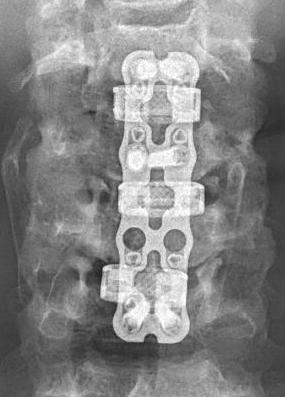

Laminectomy and Fusion

Concept

Posterior decompression is an indirect technique

- requires posterior shifting of the cord in the thecal sac

Indications

Lordotic cervical spine / no kyphotic deformity

Ossification of PLL

Instrumentation

- avoids progressive kyphotic deformity

- lateral mass screws